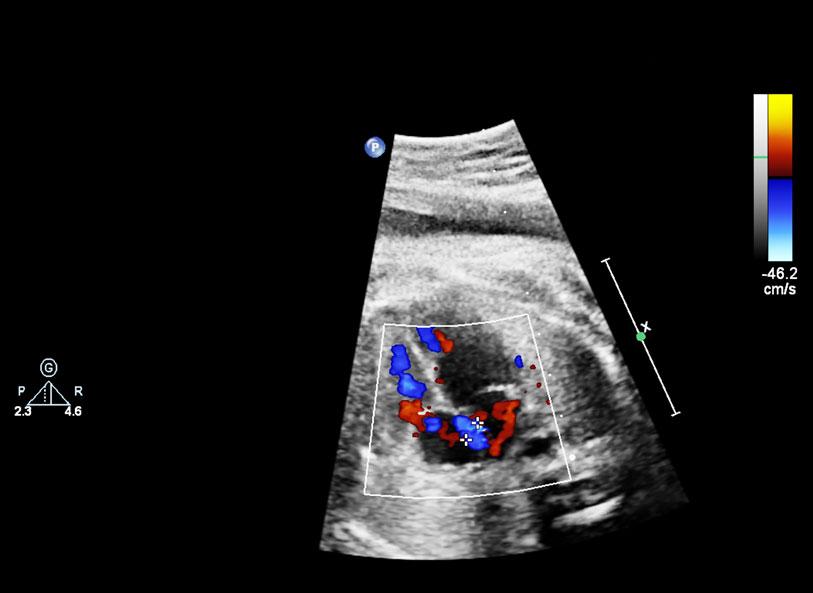

• What the heart looks like on an ultrasound